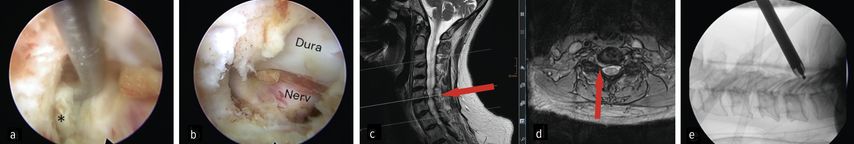

Der zervikale Bandscheibenvorfall und die Neuroforamenstenose sind weitere klinische Einsatzgebiete der spinalen Endoskopie. Insbesondere die posteriore endoskopische Foraminotomie und Diskektomien nehmen an Bedeutung zu. Die Sicherheit des Verfahrens wird durch effektive Hämostase und klare Sicht dank kontinuierlicher Irrigation unterstützt. Ruetten et al. konnten in einer RCT an 175 Patienten zeigen, dass die posteriore endoskopische Foraminotomie im Vergleich zur ACDF ein gleichwertiges neurologisches Ergebnis erzielt, bei erhaltener Beweglichkeit des operierten Segmentes.28 In unserer Abteilung wird die Technik bei ossären Neuroforamenstenosen und intraforaminären Bandscheibenvorfällen gewählt. Abbildung 7 zeigt einen intraforaminären Diskusprolaps C6/7 rechts im präoperativen MRI (c, d), die endoskopische Sicht auf Duralsack, Nervenwurzel C7 rechts und Sequester (Stern, a) in der Nervenachsel (a) sowie die Ansicht auf die dekomprimierte Wurzel (b). Des Weiteren zeigt sie eine intraoperative Positionskontrolle während der medialen Facettenresektion C6/7 (e).